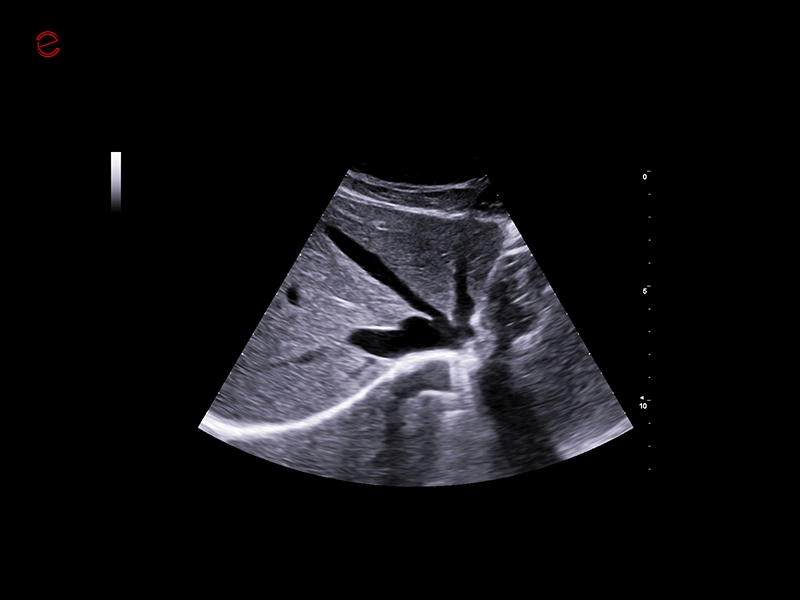

MyLab™9 Platform - High resolution imaging in testis

MyLab™9 Platform - High resolution imaging in testis